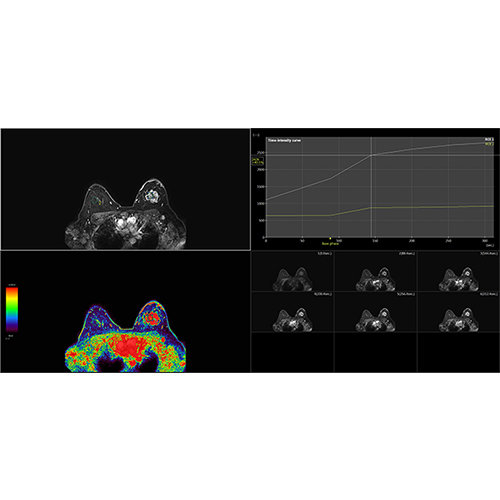

View X-Ray CT & MRI Scans Fast and Easily

Designed for surgeons, Pro Surgical 3D makes it easy to view patient scans quickly. Pro Surgical 3D facilitates the optimal 3D treatment and assessment workflows based on X-ray CT and MRI scans – and best of all, it’s FREE!

Designed mainly for CT and MR DICOM modalities.

Performs 3D reconstruction and volume rendering.

Multi-planar slicing.